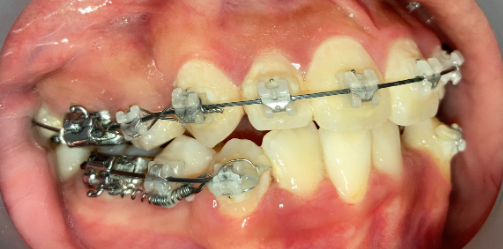

インプラントアンカー装着中の矯正治療経過|奈良の矯正歯科

アンカー装着中